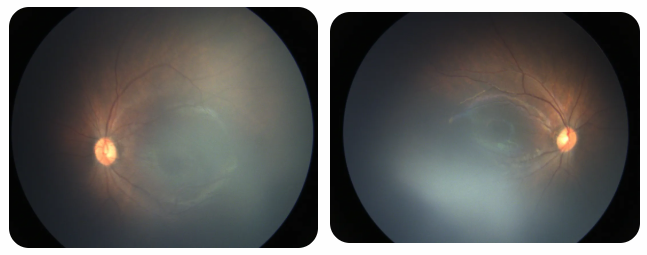

廈門眼科中心黎曉新名醫(yī)工作室曾接診一名31周出生的早產(chǎn)兒,出生體重僅1300克。由于家長缺乏篩查意識,直到孩子5個月大時眼睛仍不會追光,才前來就診。檢查發(fā)現(xiàn),患兒ROP已進展至4B期,因纖維血管增殖牽拉導致視網(wǎng)膜脫離,錯過了最佳治療窗口。盡管黎曉新教授團隊成功實施了玻璃體切割手術,孩子的視力仍存在不可逆損傷。此后,孩子開啟了長期隨診復查、治療的“護眼征程”,目前其右眼矯正視力為0.6,左眼為0.8。

近期術前檢查:

早產(chǎn)兒視網(wǎng)膜病變

術后復查: